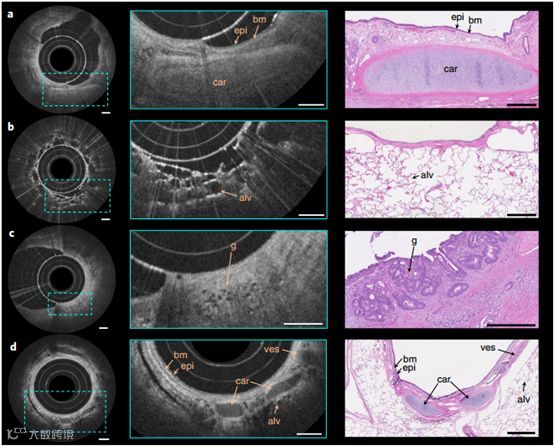

a-d,使用纳米光学内窥镜对绵羊上呼吸道(d)的离体人肺切除术(a-c)和体内的内窥镜成像。在放大的OCT图像(中间)中清晰可见肺组织的结构特征,可以辨别出细小的特征,包括小的不规则腺体(g),即腺癌的标志。